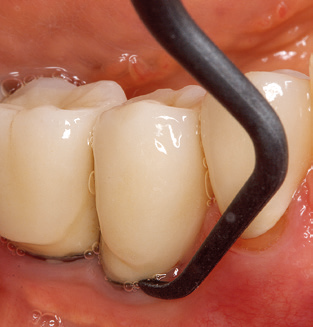

Of course, working tips for the cleaning of implant surfaces are also indispensable for SPT in patients fitted with implants. The implant cleaning attachment on the system used here is characterised by its tapered, hexagonal design. This design allows light, atraumatic penetration of the peri-implant pocket and displays a good cleaning performance (Fig. 7).